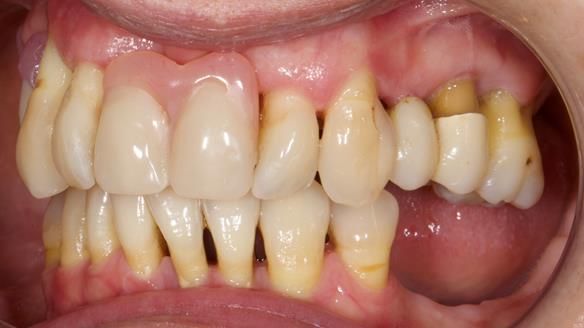

She had previously suffered from generalised periodontitis – stage IV, grade C, currently stable, with reduced attachment across the upper arch.

By the time she came to me, her periodontal condition was stable — but the aesthetics in the upper jaw were very poor.

Dr Syed Abad — my colleague and a Specialist in Periodontics — had successfully stabilised her gum health.

We provided her with an immediate upper denture (Mk 1), followed by a definitive metal-based upper denture (Mk 2). A lower removable partial denture was discussed, to be made only if needed once the upper treatment was complete. However, at review, this wasn’t necessary — Adnana had excellent neuromuscular control and function, even with a shortened dental arch (SDA).